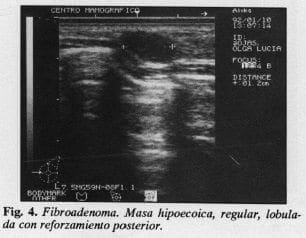

Nos da más infonnación en casos de senos densos y juveniles; evalúa adecuadamente las masas visualizadas en la mamografía dándonos datos de su consistencia sólida (Fig. 4) o quística (Fig. 5), de sus contornos regulares o no (Fig. 6), de sus paredes internas en el caso de quistes (Fig. 5) si son suaves, engrosados o con masas vegetantes (Fig. 7), nos infonna el estado ductal, ocasionalmente es posible observar la vascularidad de una masa (Fig. 6), también visualiza zonas de atenuación correspondientes a zonas de fibrosis de alto riesgo; igualmente nos suministra infonnación en una mastitis, de la fonnación de un absceso, pennite la localización prequirúrgica expedita de masas impalpables (Fig. 8), el drenaje de quistes, la realización de citologías por aguja fina o biopsias por aguja fina (Figs. 9 y 10). Es complemento indispensable a la mamografía en caso de prótesis.